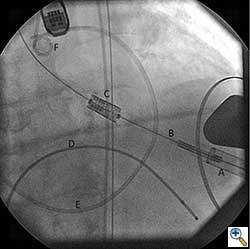

A cut-down is then performed in the ipsilateral groin and the femoral artery is exposed. Using a 18 gauge needle, wire access is achieved in the femoral artery using Seldinger technique. A 14 Fr sheath is then placed in the femoral artery. Using a straight wire through an AL1 guide catheter (Boston Scientific Corporation, Massachusetts), the stenotic aortic valve is crossed and images are obtained to assess the left ventricular outflow tract, the native aortic valve and its relation to the coronary ostia. The AL1 guide catheter is then advanced into the left ventricle and the straight wire is then exchanged for a stiff wire such as an Extra-stiff Amplatz (Cook Medical, Indiana) or Lunderquist guidewire (Cook Medical, Indiana). Next, a balloon aortic valvuloplasty (BAV) is performed with the use of a Tyshak 22 mm balloon (B. Braun Medical Inc., Pennsylvania) to facilitate crossing of the native stenotic valve with the Edwards Sapien valve (Figure 1). BAV is performed during a short period of rapid ventricular pacing to minimize transvalvular flow and potential embolization. It is critical to stabilize hemodynamics after the valvuloplasty due to hypotension from rapid pacing and from the ensuing aortic insufficiency.